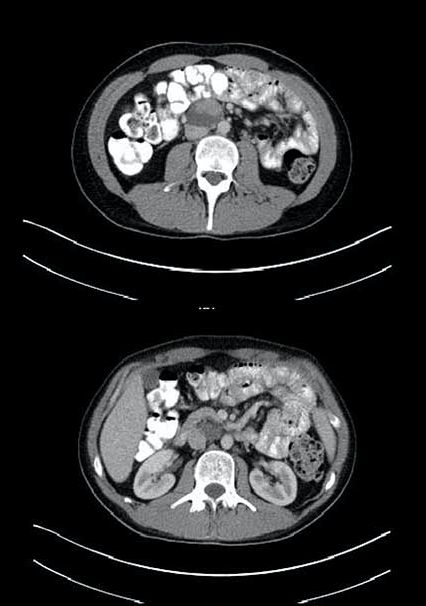

A 21-year-old man receives a stem cell transplant with high-dose salvage chemotherapy for a Stage III NSGCT refractory to primary chemotherapy. After his salvage chemotherapy, his markers normalize and his CT scan is shown. The next step is:

5

This patient has several residual masses after salvage chemotherapy. Given that he has received salvage chemotherapy and that his markers are normal, his best option is RPLND. The chance of viable disease is approximately 50%, teratoma 40%, and necrosis/fibrosis only 10%, thus, observation is a poor choice. A PET scan would not tell about teratoma which would need to be resected. A percutaneous biopsy could have sampling errors and would not obviate the need for additional treatment. Since the markers are normal, there is no indication at this time for additional chemotherapy especially in the salvage setting.